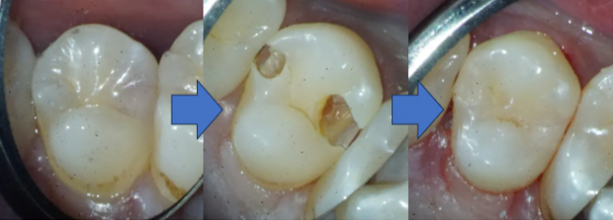

【図説あり】患者さんには見えない、虫歯治療でレジンの「つめ方」の話

歯と歯の間の大きな虫歯。当院独自の治療法で高価なセラミックを回避した症例